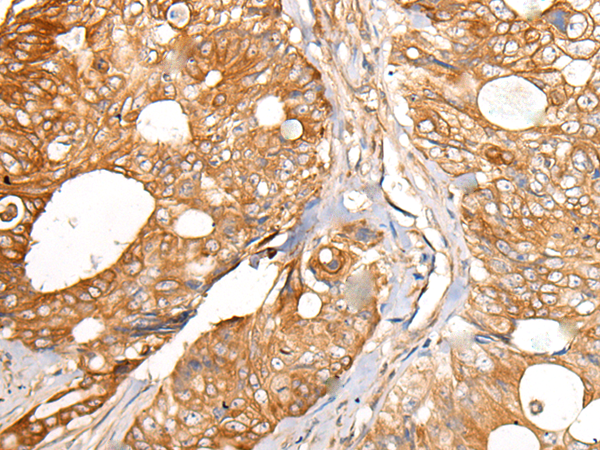

ELISA, IHC |

IHC positive control: |

Human colorectal cancer and human thyroid cancer |

IHC Recommend dilution: |

25-100 |